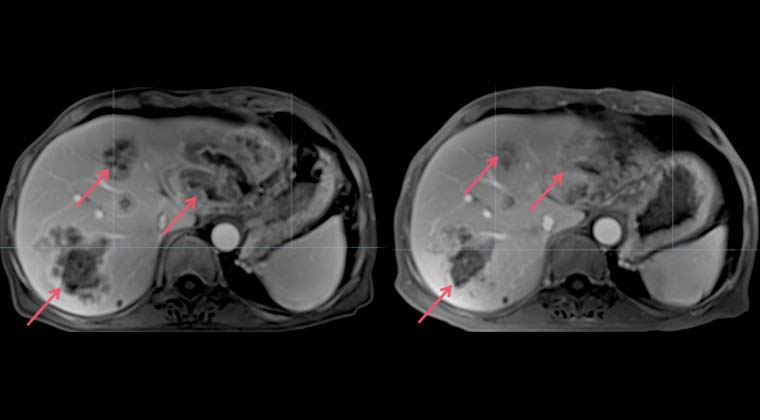

Левое изображение: 2024-08-20, множественные очаги в печени

Правое изображение: 2024-10-14, очаги в печени заметно уменьшились и стали меньше по числу